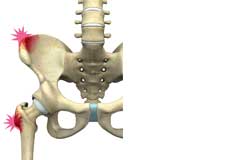

Greater Trochanteric Pain Syndrome

GTPS, also called trochanteric bursitis, is a localized painful condition affecting your outer thigh and hip area where the pain is typically confined to only the outer side of the femur at the edge of the hip.

Trochanteric Bursa Injections

A trochanteric bursa injection is a minimally invasive procedure in which medicine is injected directly into the trochanteric bursa in the hip joint using a thin needle and syringe to relieve pain and inflammation. The injection usually contains a combination of numbing medicine and cortisone (an anti-inflammatory agent). Trochanteric bursitis, also known as greater trochanteric bursitis or hip bursitis, is the main indication for a trochanteric bursa injection.